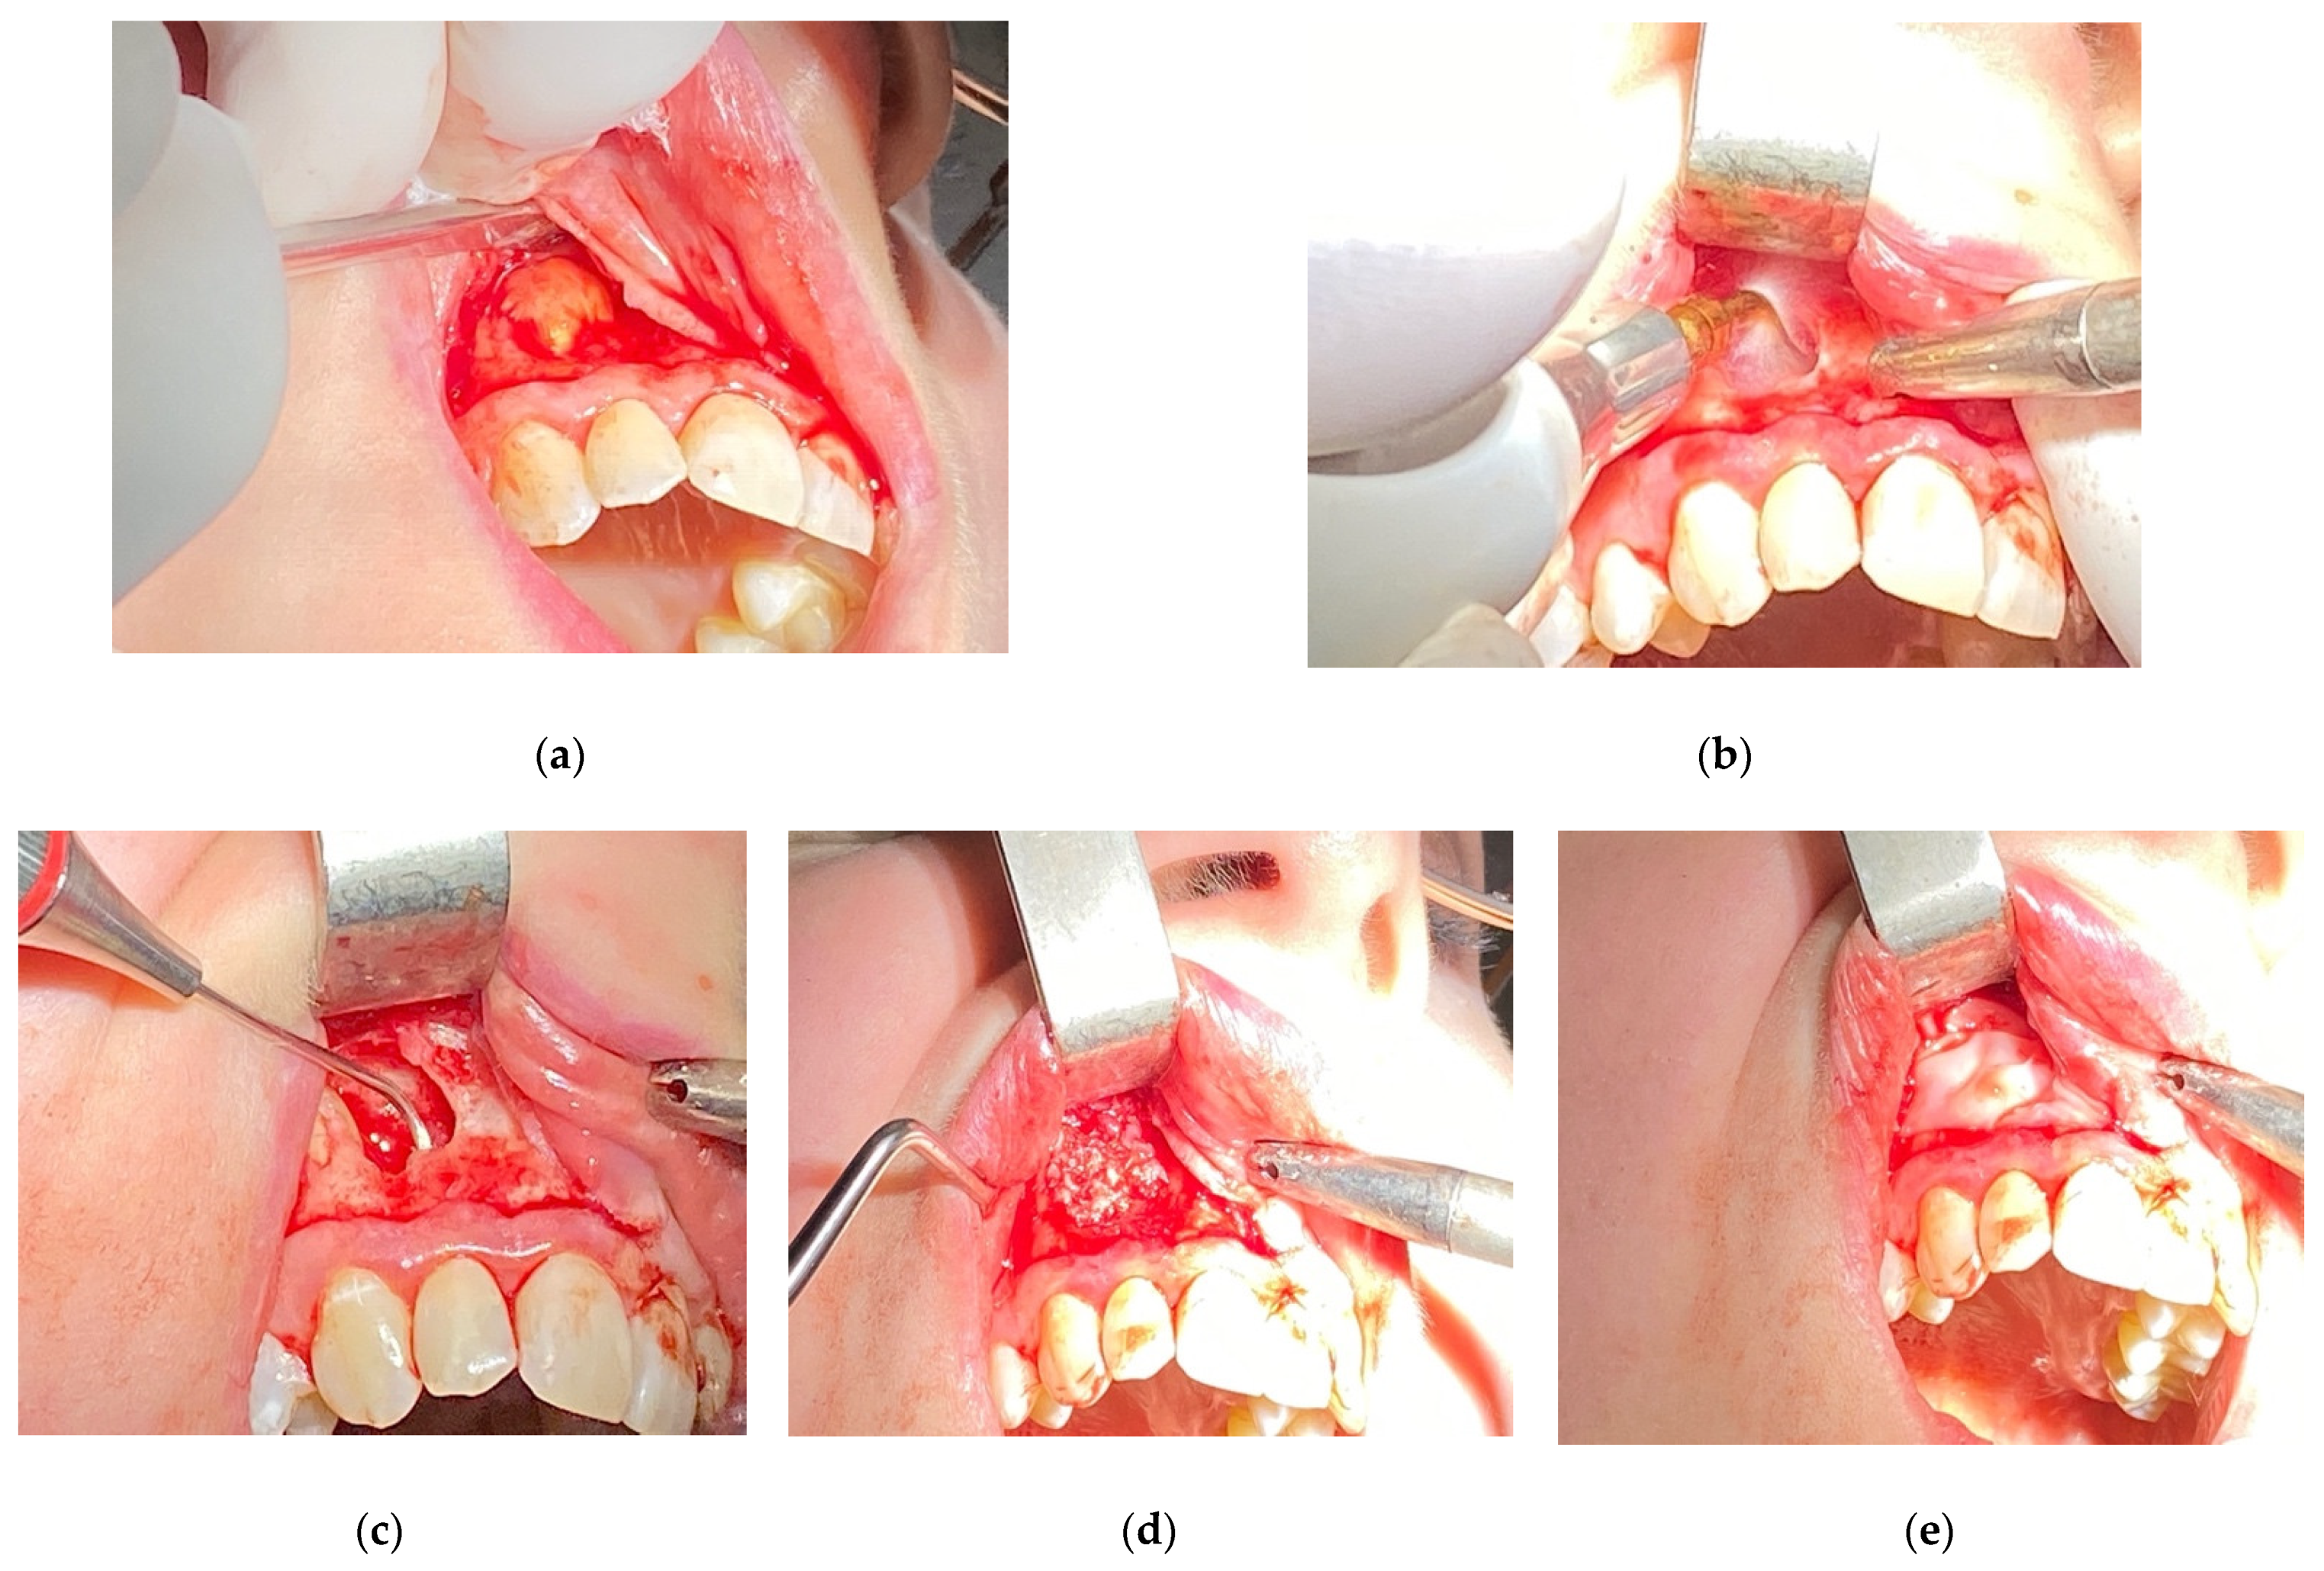

2. Materials and Methods